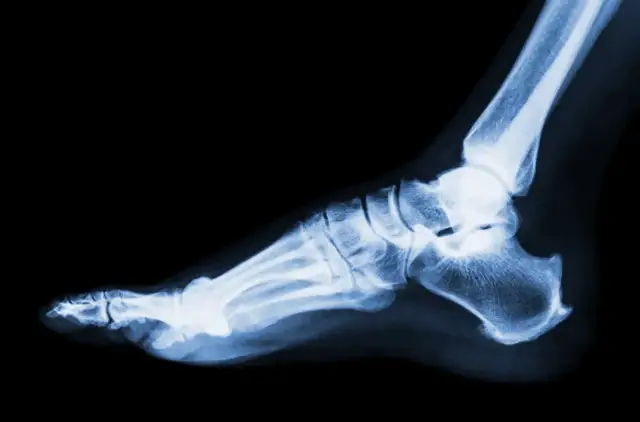

Skuteczne metody, jak pozbyć się opuchlizny po skręceniu kostki. Dowiedz się, jak szybko wrócić do formy dzięki naturalnym sposobom i rehabilitacji.

Poznaj, jak długo boli noga po skręceniu oraz jakie są objawy i rehabilitacja. Dowiedz się, co wpływa na czas powrotu do zdrowia.

Dowiedz się, czym smarować skręconą kostkę, aby szybko złagodzić ból i obrzęk. Poznaj skuteczne maści i żele wspierające regenerację.

Zastanawiasz się, co jest gorsze: zwichnięcie czy skręcenie? Poznaj różnice, skutki oraz jak unikać powikłań zdrowotnych związanych z tymi urazami.

Znajdź odpowiednią maść na skręcenie kostki, która przyniesie ulgę w bólu i przyspieszy regenerację. Sprawdź skuteczne preparaty i ich działanie!

Skręcona kostka ile L4? Dowiedz się, ile dni zwolnienia lekarskiego przysługuje oraz jakie czynniki wpływają na czas rekonwalescencji.

Ile czasu goi się skręcenie stawu skokowego? Dowiedz się, jakie czynniki wpływają na czas regeneracji i jak skutecznie przyspieszyć powrót do zdrowia.